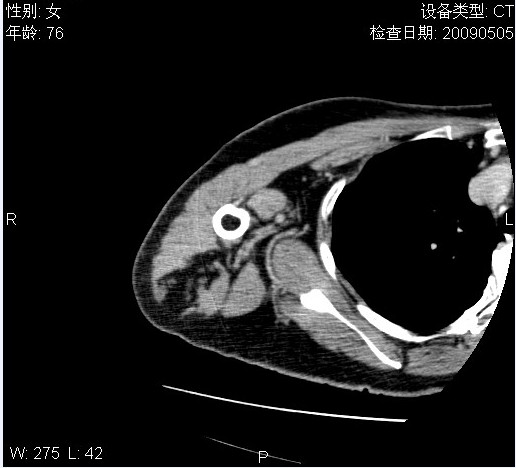

标题: CT19811:女,76岁,右上臂肿物1个月 [打印本页]

标题: CT19811:女,76岁,右上臂肿物1个月

使用了造影剂,可惜效果不太好

右肱骨上段软组织内见梭形低密度影,边界清楚,最长径约54mm.

病理结果:脂肪瘤。术中见肱骨骨膜受侵,有出血,量不详。

当时诊断意见:右肩三角肌内蔓状血管瘤(先天性动静脉瘘)。

本人对病理结果有个疑问:单纯的脂肪瘤内为什么有条状软组织影,那应该脂肪肉瘤才对啊?

该病例增强效果欠佳,由于经验欠缺,我们注射对比剂是由下肢足背静脉给药。注速2.0。虽然如此,但我们可以看到肿块内部条状软组织影是强化的,而且是连续的,并可见供血动脉是由腋动脉的其中一支即肩胛下动脉分出。从这些征象我们可以得出诊断:蔓状务血管瘤。

可病理偏偏为脂肪瘤,我怀疑取材有问题。因为蔓状血管瘤异常扩张的静脉外周是脂肪成分,它可以侵犯肌组织及骨骼。当取材于外周,那当然是脂肪瘤。此时我认为临床的最终诊断不应单从病理出发,应该综合考虑。